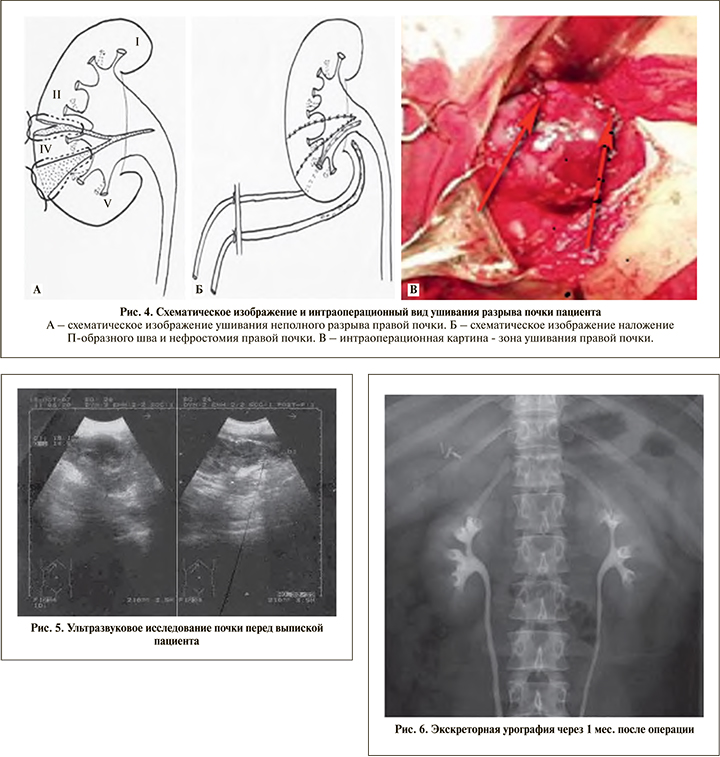

Интраоперационно установлен неполный разрыв правой почки, что послужило основанием для выполнения органосохраняющего вмешательства с восстановлением поврежденных структур почки, наложены П-образные швы атравматической нитью Викрил 3,0 (рис. 4).

Послеоперационный период протекал гладко, отмечено полное восстановление функции поврежденной почки, ребенок на 16-е сутки после операции выписан домой в удовлетворительном состоянии. Перед выпиской пациенту выполнено УЗИ почек, при котором правая почка находится в обычном месте, ее дыхательная подвижность сохранена, контуры почки ровные, нечеткие. Эхоструктура паренхимы почки: эхонеоднородная зона в проекции нижнего полюса, чашечно-лоханочная система не расширена (рис. 5). Изучение отдаленного результата после операции свидетельствует о полной сохранности функции оперированной почки (рис. 6).